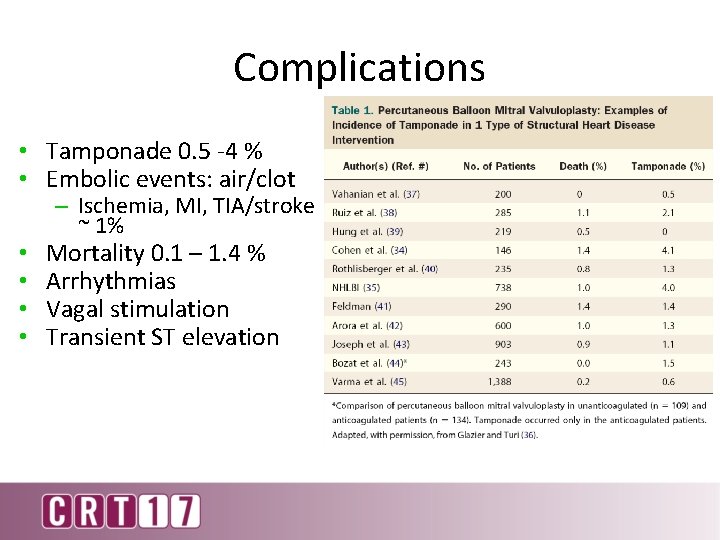

Complications • Tamponade 0. 5 -4 % • Embolic events: air/clot • • – Ischemia, MI, TIA/stroke ~ 1% Mortality 0. 1 – 1. 4 % Arrhythmias Vagal stimulation Transient ST elevation

Factors Influencing Complication Rates • Diagnostic versus interventional – Diagnostic – 1. 3% (Roelke CCD 1994) – Interventions - 3. 8% (Liu AHJ 2006) • • • Level of anticoagulation Sheath size Left atrial pressure Presence and compliance of pericardium Use of echo guidance Most important – Operator learning curve